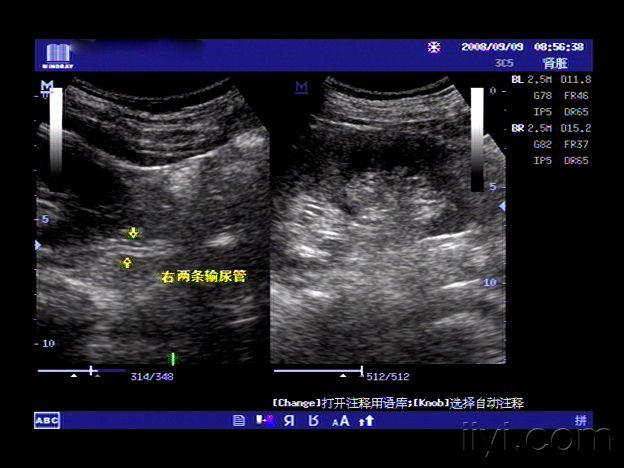

【贴图】双肾盂,双输尿管畸形

左侧双肾盂,双输尿管畸形.严重吗?怎么治疗?

双肾盂图片

肾盂分离图片

肾盂图片